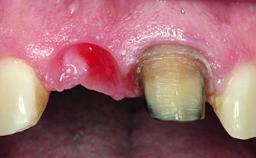

A 32-year-old female Caucasian patient with a compromised maxillary right central incisor was referred to us by a general dentist. Her chief complaints were discomfort and mobility of tooth 11 with unsatisfactory esthetics due to discoloration. The patient reported a previous trauma, some years earlier, as the origin of pathology on the afflicted tooth. Anamnesis was negative for any other dental or periodontal pathology in the remaining dentition. The patient did not take any medication and reported to be a light smoker (5–10 cigs/day). She had high esthetic expectations of her treatment. The extraoral examination revealed a high smile line with full exposure of her maxillary teeth and surrounding soft tissue in the area between the second premolars.

Soft Tissue Anatomy Intact Defective

Bone Volume Horizontally and vertically sufficient Horizontally deficient Deficient vertically or deficient vertically AND horizontally